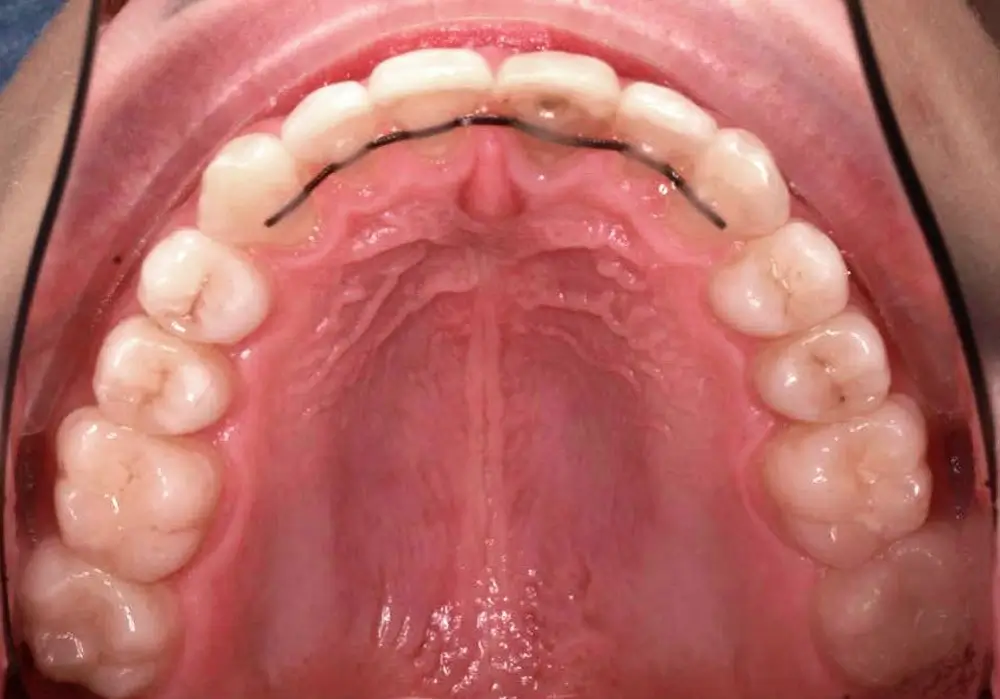

Кейс 9

Бирковская Екатерина Александровна

Количество кап ВЧ 23

Количество кап НЧ 23

ДО

ПОСЛЕ